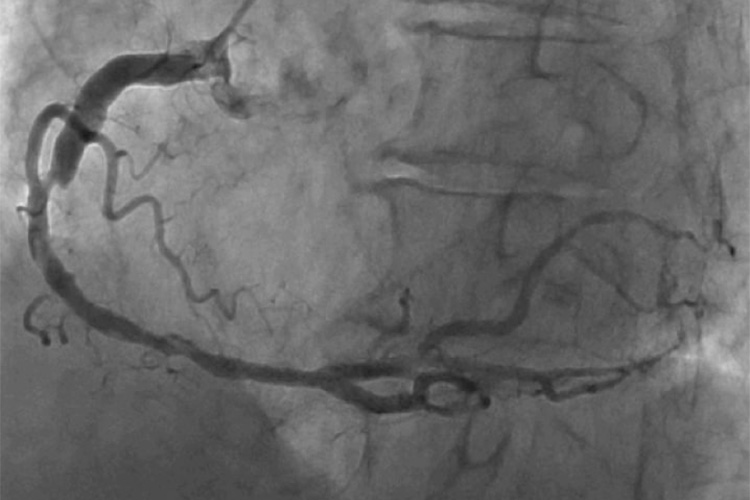

⑩冠動脈カテーテル検査

カテーテルという細長い管を手首や肘、足の付け根の動脈に通して心臓まで挿入し、造影剤を注射して冠動脈のX線撮影を行います。冠動脈の狭窄の程度、部位、病変数などを詳細に評価でき、冠動脈疾患を診断するのに最も正確な評価が出来る検査です。詰まって狭い箇所が見つかった場合は、検査に引き続いてその場でカテーテル治療を行う場合もあります。